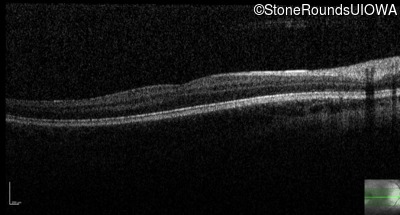

Congenital Stationary Synaptic Dysfunction (IA2g)

Age at visit:

13 years

OD

OS

20/63 -2 sc

20/63 -2

OCT Stack